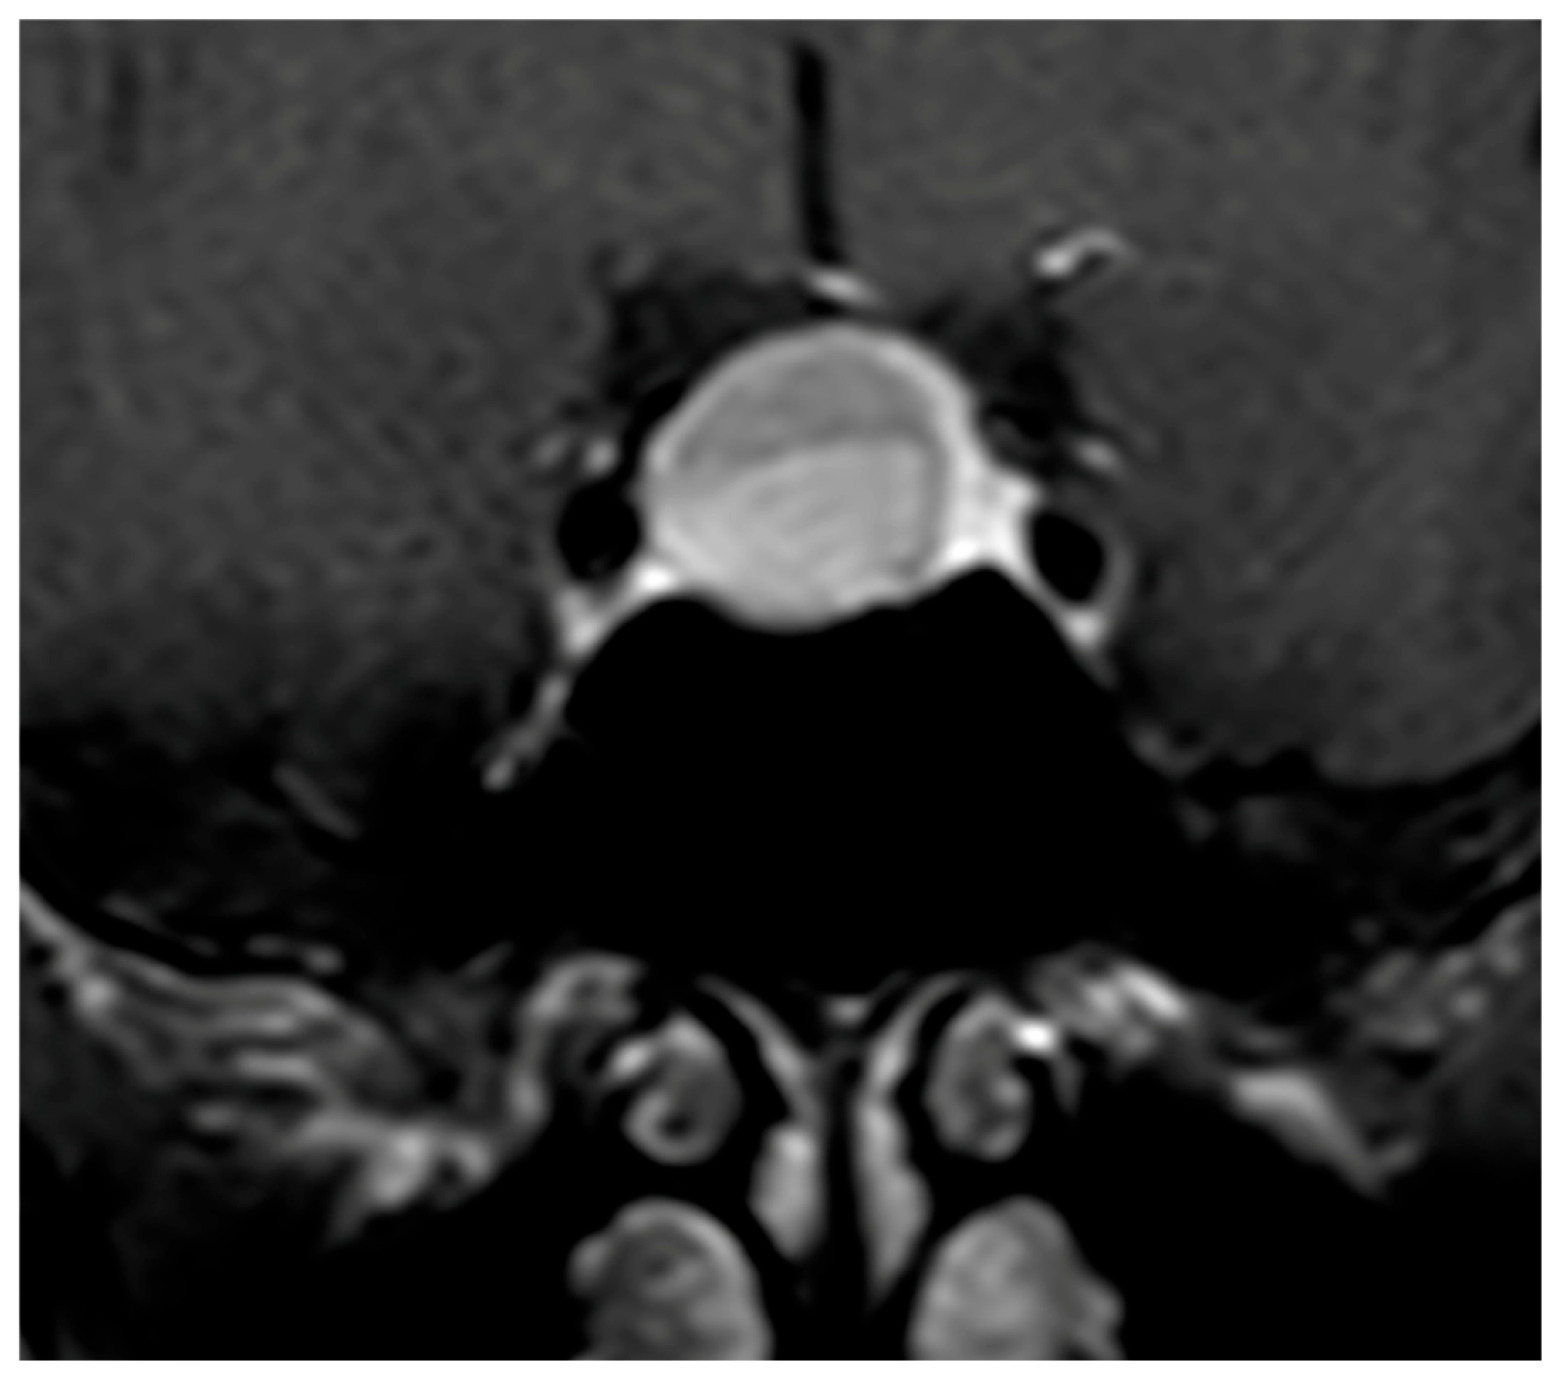

The pattern of enhancement after gadolinium injection provides an additional and highly informative contrast between both entities. Hypophysitis typically demonstrates an intense and homogeneous enhancement, reflecting diffuse vascularized inflammation, with reported rates of homogeneity ranging from 70% to 90% [37,73,74]. NFPMA characteristically show a heterogeneous and often delayed enhancement [75,76,77]. The use of early dynamic post-contrast sequences has been advocated by several authors, as it increases sensitivity for detecting subtle differences in enhancement kinetics between infiltrative and neoplastic processes (Figure 3) [78].

Figure 3. Coronal T1-weighted image after Gadolinium administration showing a NFPMA displacing the normal residual pituitary tissue leftward, which enhances homogeneously and intensely.